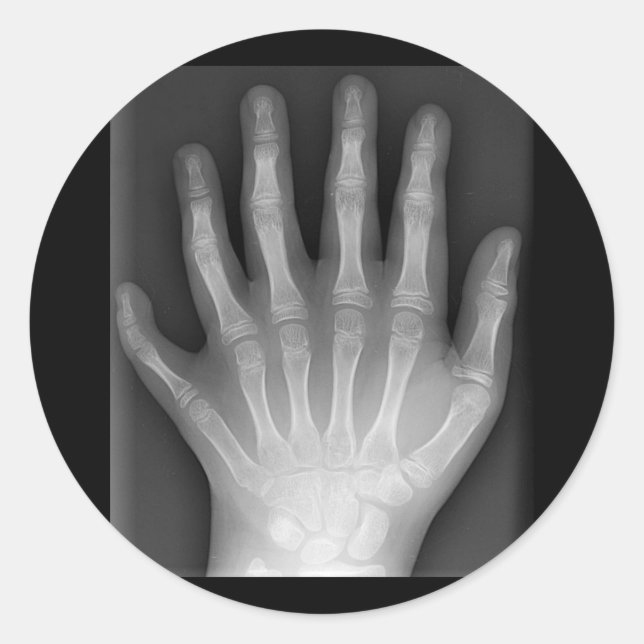

Sticker Rond Polydactylo, Six Doigts, X-Ray, rareté !

Six doigts Cette radiographie, dépouillée de marques d'identification, est présentée par Drgnu23, un podiatre qui travaille avec les défavorisés. Présenté ici est une rareté médicale - la main d'un garçon de dix ans né avec six doigts. Présentée sur un tee-shirt noir, cette image laissera les gens curieux et perplexes devant la nature de la biologie humaine.